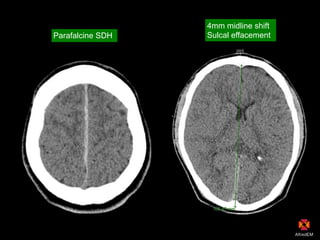

Parafalcine SDH

4mm midline shift

Sulcal effacement

CT findings Head Parafalcine andtentorium SDH, SAH 4mm midline shift Chest Bilat Ptx (L = no ICC) Abdo/Pelvis Vertical shear pelvic # (symphysis disruption) Active blush small bowel mesentery Pelvic haematoma (bladder compression) Pelvic blush at pubic symphysis Psoas haematoma with active blush (L4/5)